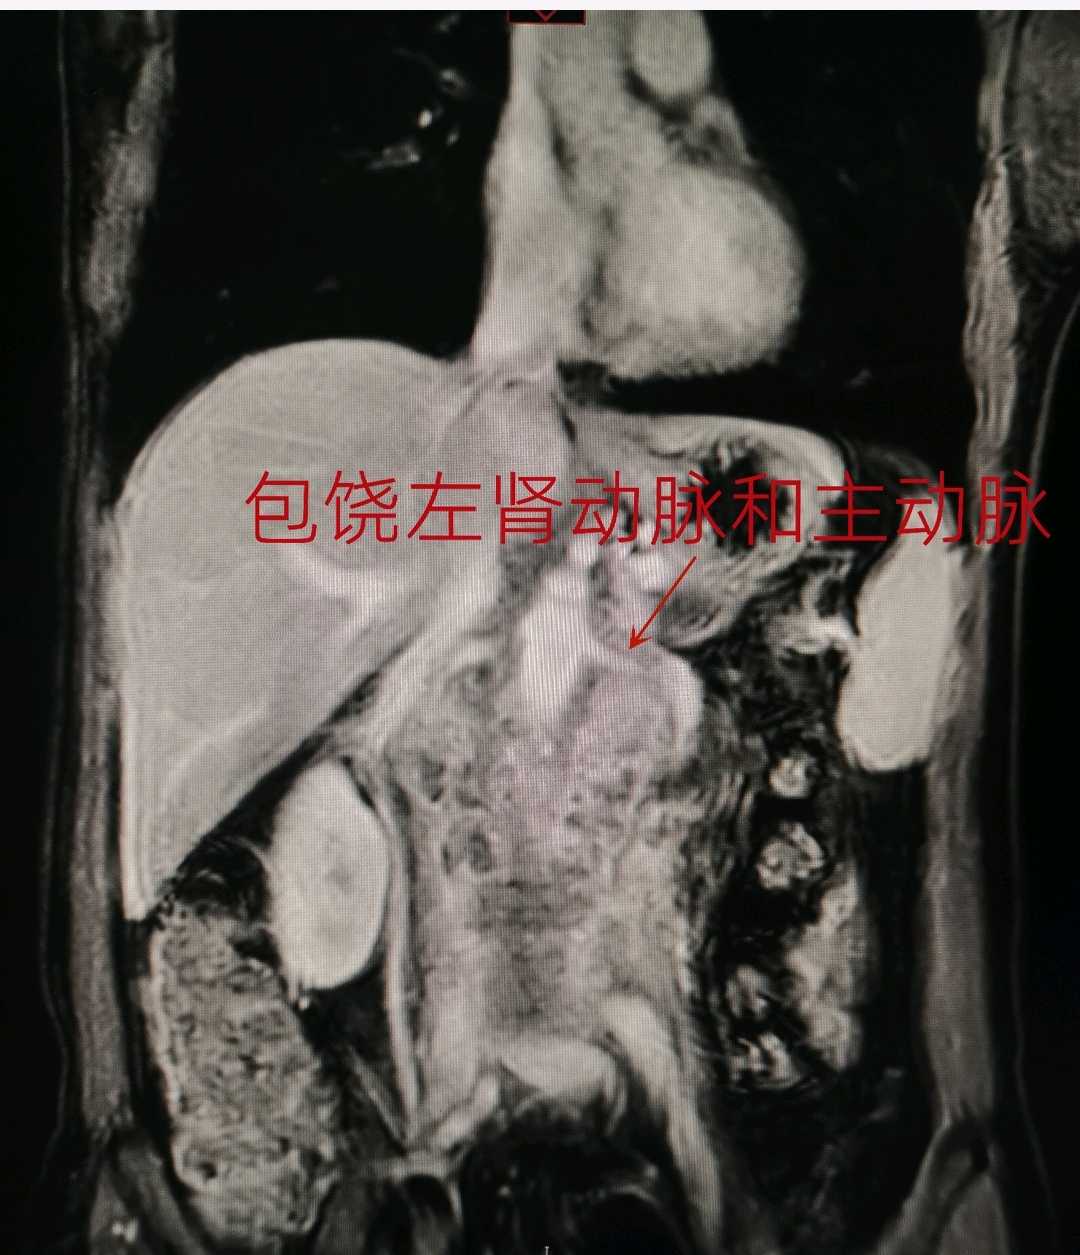

柯女士是一位45岁的中年女性,有着姣好的面容、高挑的身材和开朗的性格。2022年5月,她突然感到左侧腰背部持续疼痛,无法进食,经过一系列检查后被诊断为左侧肾盂癌伴腹膜后巨大淋巴结转移,侵及周围肌肉和腰椎,侵及左肾动脉并包绕大部分主动脉。这样在左侧腹部形成一个直径近10cm,长度超过15cm的与血管、腰肌、椎体相融合的固定不动的巨大肿瘤。

经过充分的术前准备,我们于2022年6月14日为患者进行了手术治疗,术中切除了左侧肾脏、肾上腺、主动脉周围淋巴结、肿瘤侵犯的肌肉和部分腰椎横突;肿瘤侵及的部分主动脉,也进行了部分切除和修补(注:主动脉是人体最大动脉,一般只有心脏和大血管外科医生能进行修补),并在腰椎侵犯处放钛夹标注将来放疗部位。